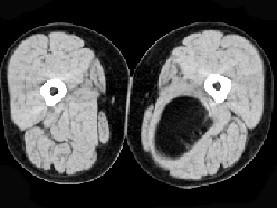

问题 女性,52岁,感左小腿肿胀两年余,活动后稍加重,不痛不热,请结合所提供的图像,选择最佳答案 ( )

选项 A、大腿囊肿 B、大腿脂肪瘤 C、大腿畸胎瘤 D、大腿平滑肌瘤 E、大腿错构瘤

答案 B